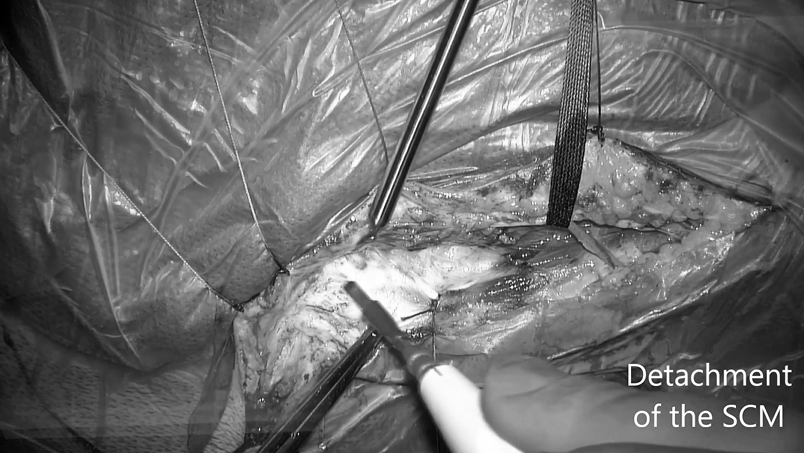

▼小骨窗开颅显微(简称SCM)分离,将胸锁乳突肌从乳突上分离,从而允许向后收缩。